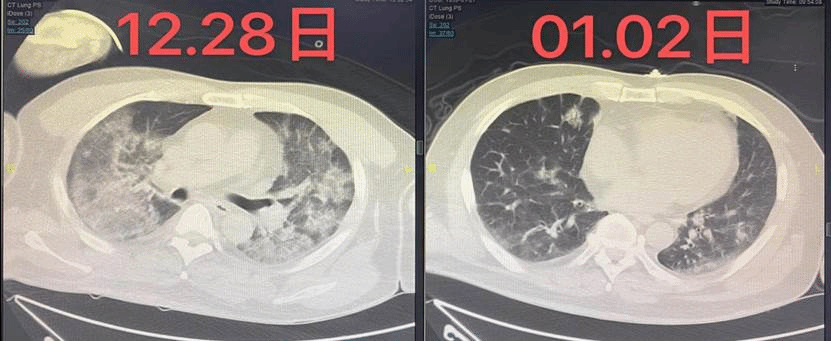

经过全体医护人员的12天的艰难救治,患者的氧合指标逐渐上升,双肺渗出影像显著吸收,肺氧合功能显著改善,逐步脱离高流量吸氧及鼻导管吸氧,脱氧状态下,血氧饱和度稳定在95%以上,一般状态改善、生命体征趋于稳定,老人的生命,转危为安!